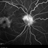

- Weiss ring, fluorescein leakage, fluorescein angiogram (FA), Heidelburg Spectralis, 30 degrees, optic nerve, uveitis, sarcoidosis, cystoid macular edema (CME)

- Fluorescein angiogram of a 55-year-old female with a Weiss ring affecting her right eye. Patient was diagnosed with sarcoidosis. She has cystoid macular edema secondary to panuveitis.